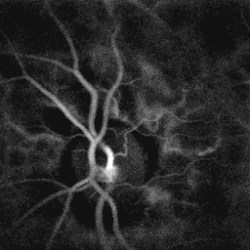

The diagnosis of branch retinal vein occlusion is made clinically by finding retinal hemorrhages in the distribution of an obstructed retinal vein.

- Fluorescein angiography is a helpful adjunct. Findings include delayed venous filling, hypofluorescence caused by hemorrhage and capillary nonperfusion, dilation and tortuosity of veins, leakage due to neovascularization and macular edema.